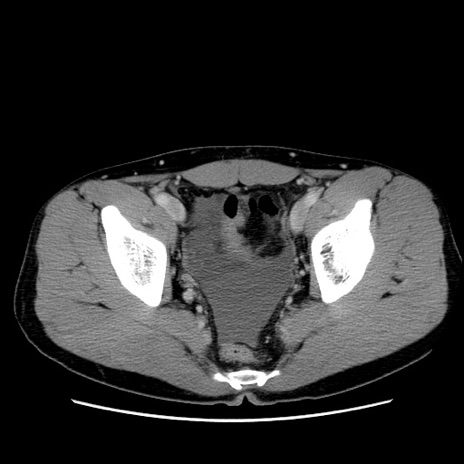

症例36(横断像)

【症例】20歳代 男性

【主訴】心窩部痛

【現病歴】今朝より上腹部痛あり。一旦軽快していたが再度出現したため救急要請。昨日夕に白身の魚を含む刺身を食べた。

【身体所見】BP 136/89mmHg、HR 74/min、BT 37.0℃、腹部:膨満、軟、心窩部に圧痛あり。反跳痛なし、筋性防御なし、腸雑音やや亢進あり。

【データ】WBC 17700、CRP 0.48